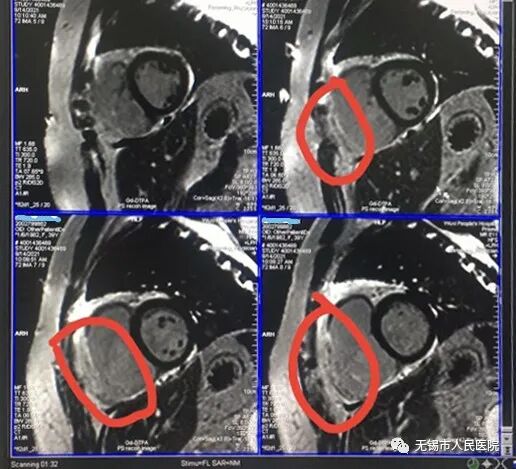

患者听到自己有心脏病感到非常的诧异!据她自己所述,之前在外院多次检查从未说过她心脏有问题,也没有觉得心脏有任何不适,并且已经生育两个孩子。但她还是听从了钱主任的建议,做了心脏核磁共振检查。核磁共振显示病人右室游离壁心肌缺失,取而代之的是脂肪纤维组织,最终证实了钱主任和过主任的判断。